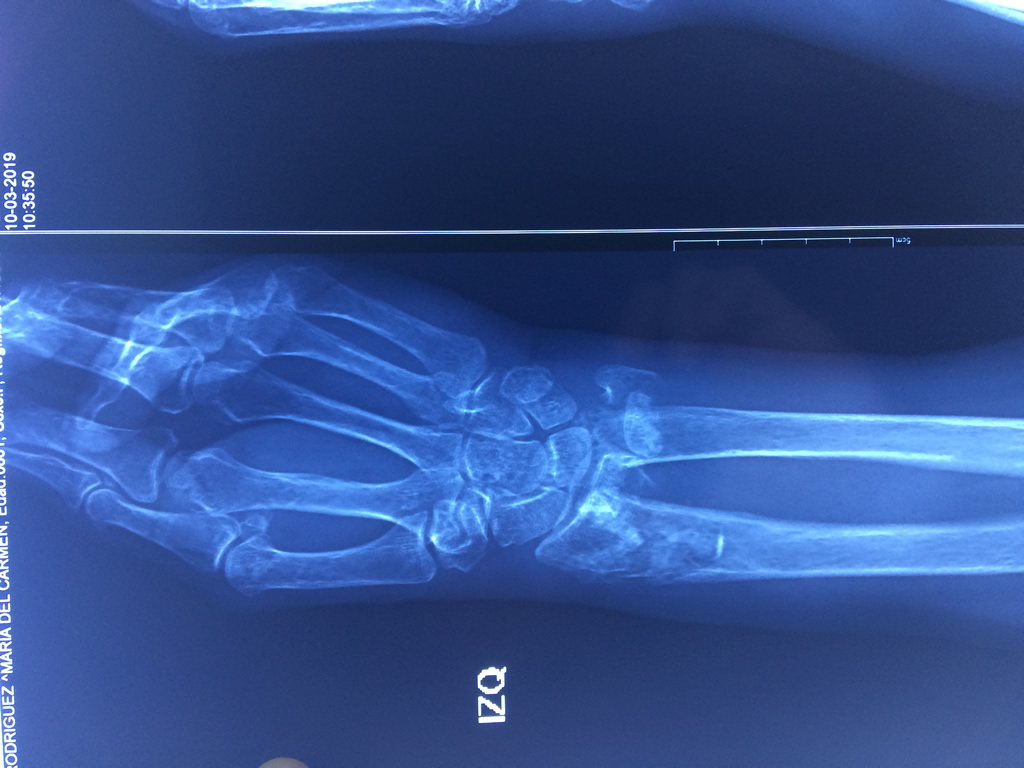

Cirugías de Codos - Cirugías de Muñecas y Manos

Los procedimientos más comunes en cirugía de la mano son aquellos destinados a reparar traumatismos, incluyendo lesiones de tendones, nervios, vasos sanguíneos, y articulaciones; huesos fracturados; y quemaduras, cortes, y otros daños de la piel.